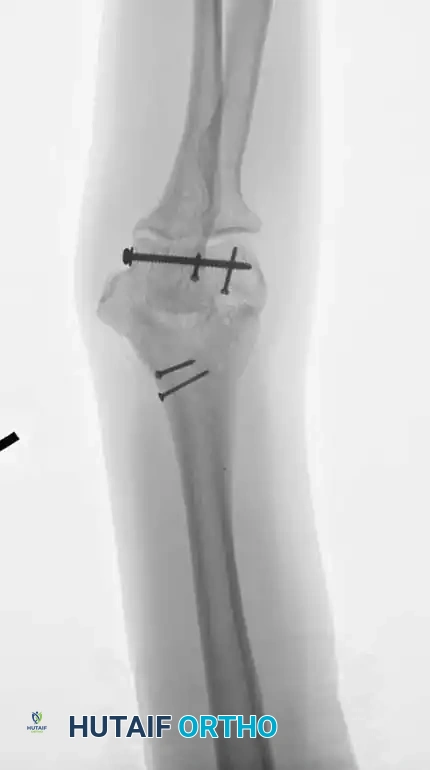

Image

Fig. 3: Supracondylar fracture with intra-articular extension fixed with 90-90 locked plates through an olecranon osteotomy approach, and subsequent hardware removal.

However, modern biomechanical studies (e.g., Self et al., Schemitsch et al.) have demonstrated that parallel plating (direct medial and direct lateral plating) provides superior resistance to torsional forces and axial loading, particularly in the presence of severe metaphyseal comminution. Precontoured anatomical locking plates have largely replaced one-third tubular and 3.5-mm reconstruction plates, which are prone to fatigue failure in complex patterns.